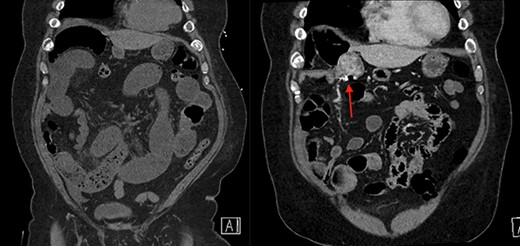

On the left is the initial CT scan non-contrast demonstrating dilated small bowel loops and a transition point in the right lower quadrant. On the right is the CT angiography (CTA), performed a week later, showing a mass and pill cam in the right upper quadrant.

On the left is the initial CT scan non-contrast demonstrating no obvious mass. On the left is the CTA, a week later, showing a mass and pill cam in the right upper quadrant.

The next week, unbeknownst to his Gastroenterologist about his recent small bowel obstruction admission, he then proceeded with a capsule endoscopy study to assess for other causes of his anemia. He tolerated the pre-operative bowel preparation without issues. After swallowing the capsule, he subsequently had bloody bowel movements. He then went to the ER and found to have a hemoglobin of 7.1, which was decreased from his prior week’s hospitalization, 8.4. A CT angiography (CTA) abdomen and pelvis was then performed that showed a 4 × 6 × 4.1 cm mass in the right upper quadrant with the capsule endoscopy at the level of the mass (Figs 1 and 2). The images from the capsule were unremarkable. On review of his imaging with radiology, it appeared that this mass was not apparent without IV contrast on his previous CT scan a week prior. In addition, a prior CT abdomen pelvis with IV contrast 10 months ago was negative for a small bowel mass. A repeat abdominal and pelvis CT with oral and IV contrast was done for confirmation. This re-demonstrated the 6 cm mass with the capsule stuck proximal to it; therefore, we performed a diagnostic laparoscopy.